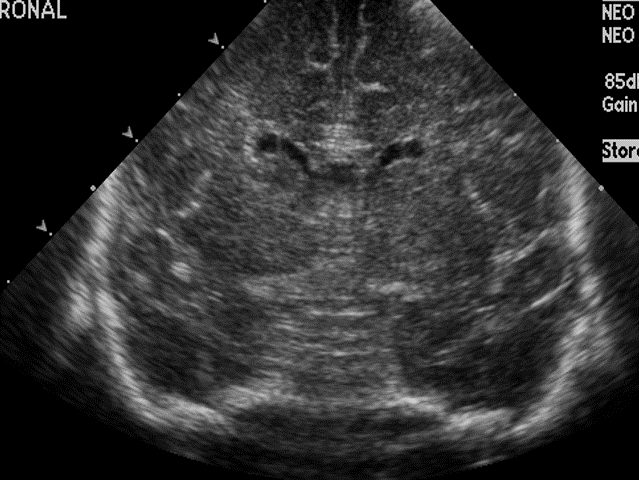

CSF spaces/ventricular system

There is a prominence of the extra axial fluid spaces. [Yes/No]

There are debris/septations in the extra axial fluid spaces. [Yes/No]

There is prominence of the ventricular system. [Yes/No]

There is an asymmetry of the ventricular system. [Yes/No]

There is a cavum septum pellucidum. [Yes/No]

There is a midline shift towards right/left. [Yes/No]

The lateral ventricle/s are dilated. [Yes/No]

The third ventricle is dilated. [Yes/No]